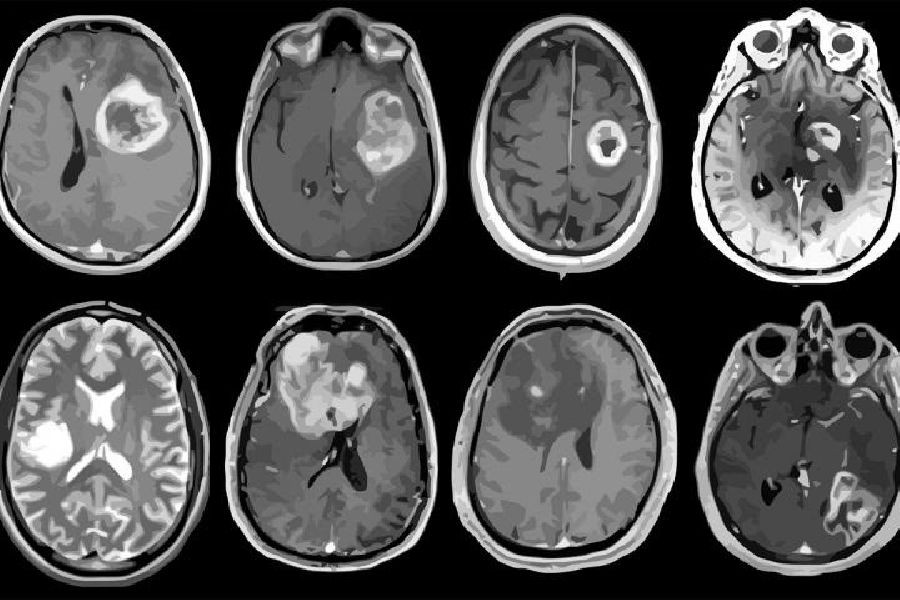

Ensayan un nuevo `fármaco` experimental que mata las células tumorales en humanos con glioblastoma

Un ensayo clínico inicial en personas con el cáncer cerebral mortal, el glioblastoma, ha demostrado que un fármaco experimental de ácido nucleico esférico (ANE) desarrollado por científicos de la Universidad Northwestern, en Estados Unidos, pudo atravesar la barrera hematoencefálica y provocar la muerte de células tumorales.

El estudio de fase 0 se realizó con ocho personas que tenían glioblastoma recurrente en el Centro Integral de Cáncer Robert H. Lurie de la Universidad Northwestern. En la fase 0, los investigadores usan una pequeña dosis de medicamento para asegurarse de que no sea dañino para los humanos antes de comenzar a usarlo en dosis más altas en ensayos clínicos más grandes.